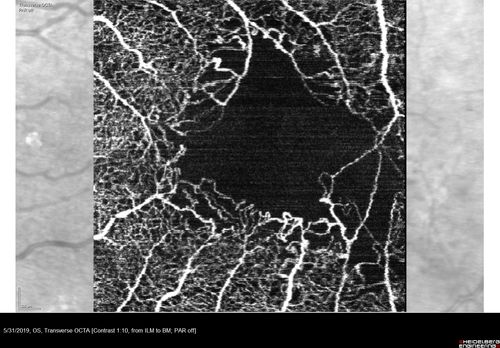

Diabetic Macular Ischemia - Enlarged FAZ - OCT-A

70 year old female diagnosed with diabetes 2 years ago. Her blood pressure was normal at 116/73. She has vision loss for 6 months in both eyes. VA is 20/100 OU. OCT-A shows macular ischemia.